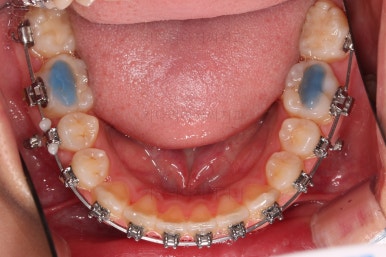

부산치아교정치과 초진 시 입안의 모습입니다.

앞니쪽이 위아래 모두 삐뚠 상태였고요.

왼쪽은 덧니로 툭 튀어나가 있고, 상대적으로 작은 앞니는 안으로 말려 들어가 아랫니와도 거꾸로 물리는 상태였습니다.

장치를 처음 부착했고요.

이번 환자분이 선택한 장치는 윗니는 세라믹 자가결찰인 엠파워 클리어, 아래는 메탈 자가결찰인 엠파워 메탈입니다. 둘 다 같은 회사의 같은 세팅의 장치이므로 혼용이 가능하죠. 대신 비용은 좀 더 줄일 수 있습니다.